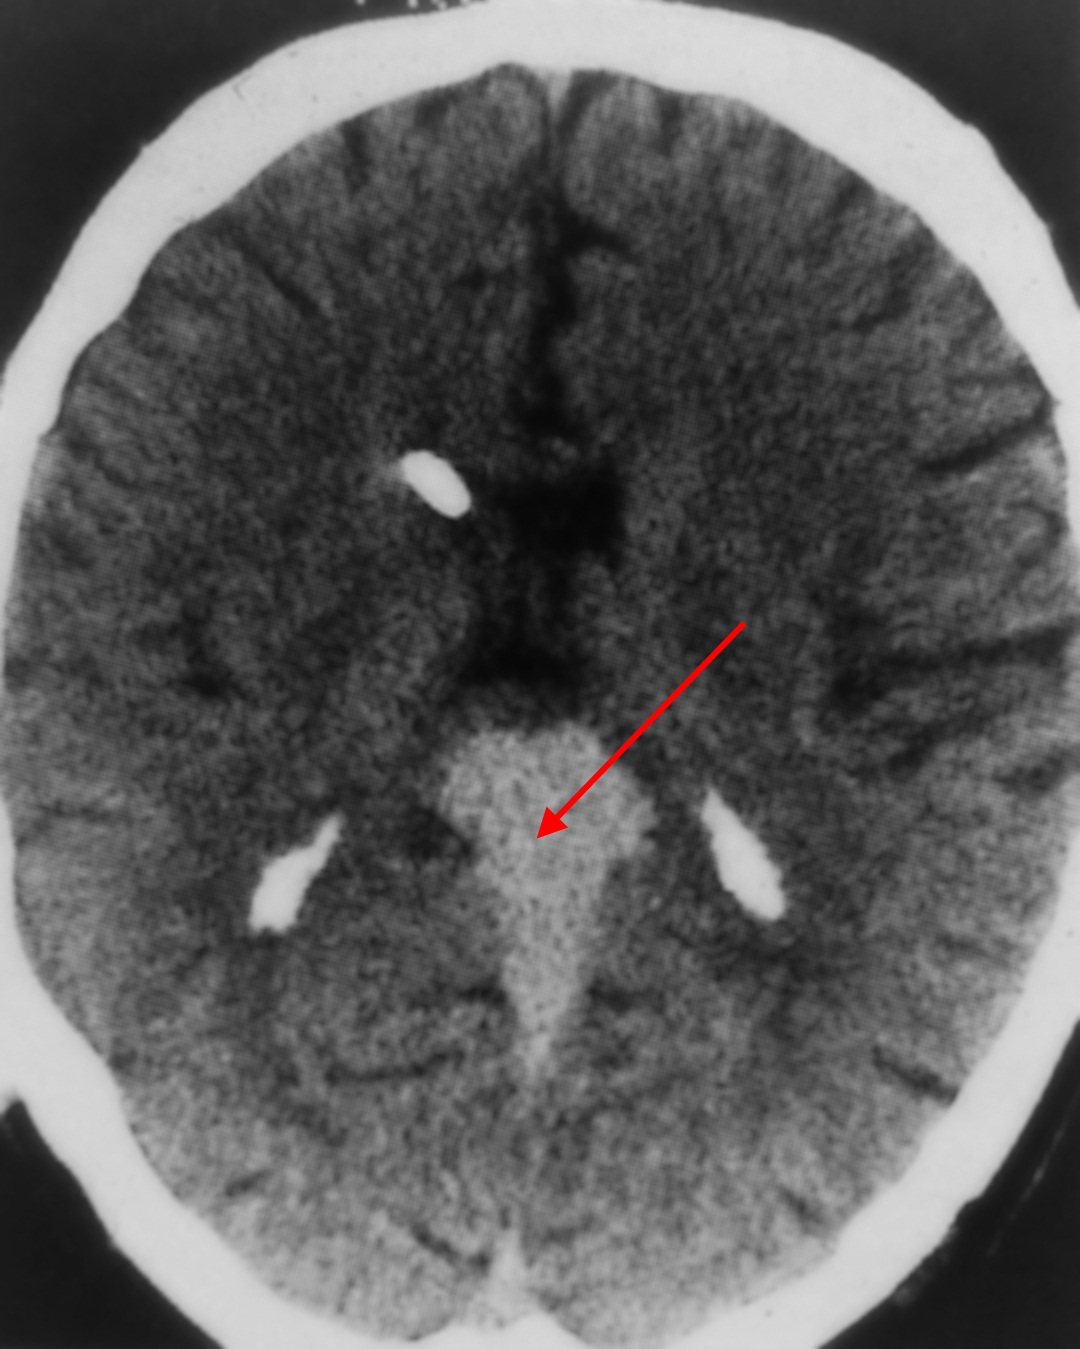

Иллюстрации и пояснения: гиподенсивный очаг на КТ головного мозга